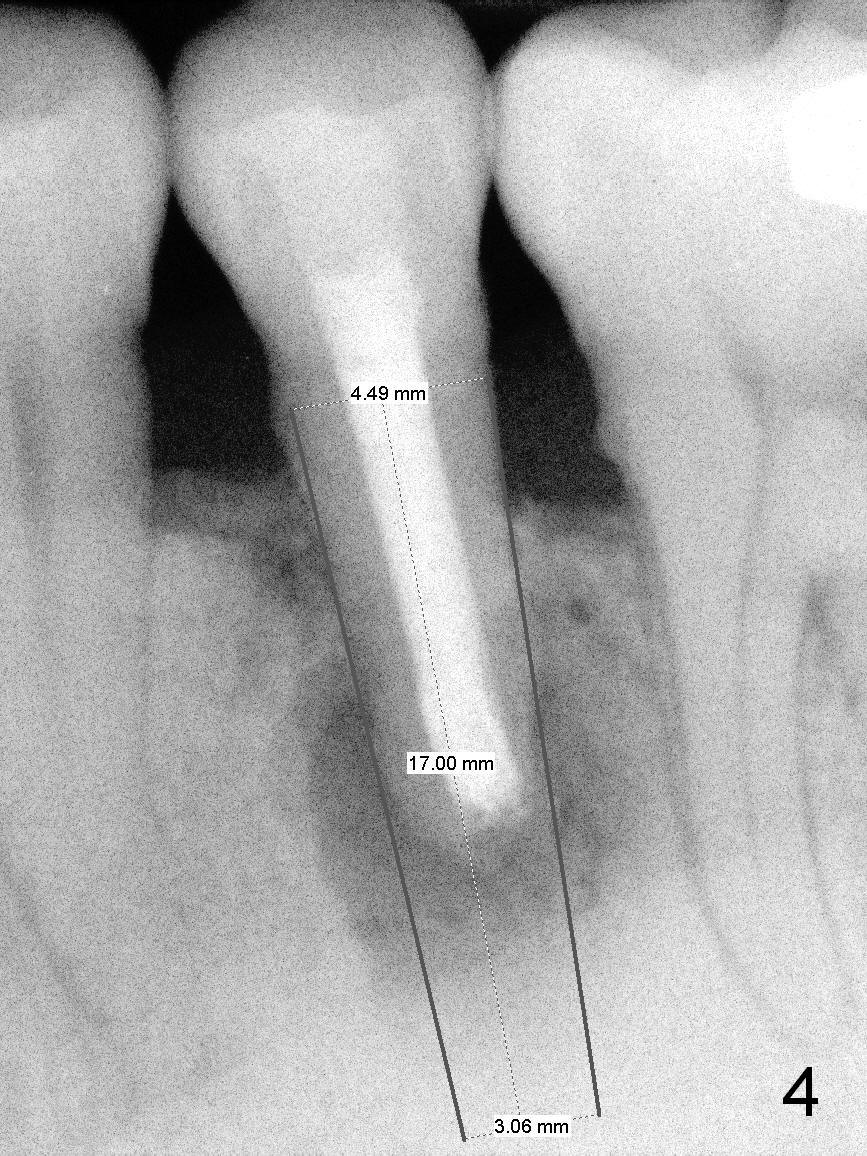

A 45-year-old man (JT) has endo failure at #20 with fenestration (Fig.1,2 black >) and fistula (white <). Insertion of a Gutta Percha at the fistula (Fig. 3 <; PA taken 2 years ago) indicates that the infection is dervied from the apex of the tooth #20. The socket will be soaked with 2% Xylo, 1:50,000 Epinephrine gauze. A 4.5x17 mm tissue-level (Fig.4) or 14 mm bone-level implant is placed as lingual as possible (Fig.5 green). If primary stability is achieved, an abutment is placed (pink). A large piece of resorbable membrane is used to cover the buccal defect (including buccal recession, fenestration and fistula (Fig.6 yellow dashed line). Two small pieces of non-resorbable membrane are placed to cover the gingival recession and the fenestration (Fig.7 white dashed line, buried underneath the edge of the gigniva). Then place bone graft buccally. Place a small piece of gauze (one layer) or plastic (from Tatum implant bag) over the 2nd membrane over the gingival recession and fabricate an immediate provisional. When the acrylic is partially set, remove the gauze or plastic from the provisional. After trimming and polishing, the provisional is cemented to securely keep the 2nd membrane in place. When the wound is healing and the 2nd membrane is stable, trim the buccal extension of the provisional. It is expected that the buccal hard and soft tissue will regenerate over the implant.